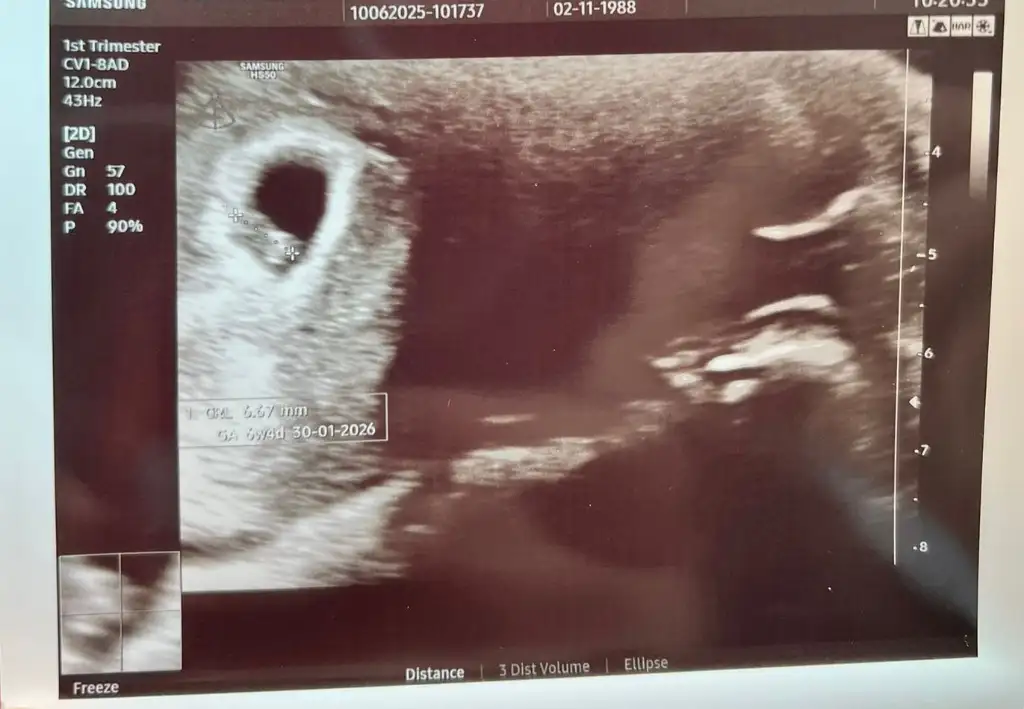

Benimkine de bir baksanız 6+4'tü burda karından ultrason.

• WhatsApp Image 2025-06-12 at 11.42.31 (1).webp

WhatsApp Image 2025-06-12 at 11.42.31 (1).webp

30,8 KB · Görüntüleme: 16